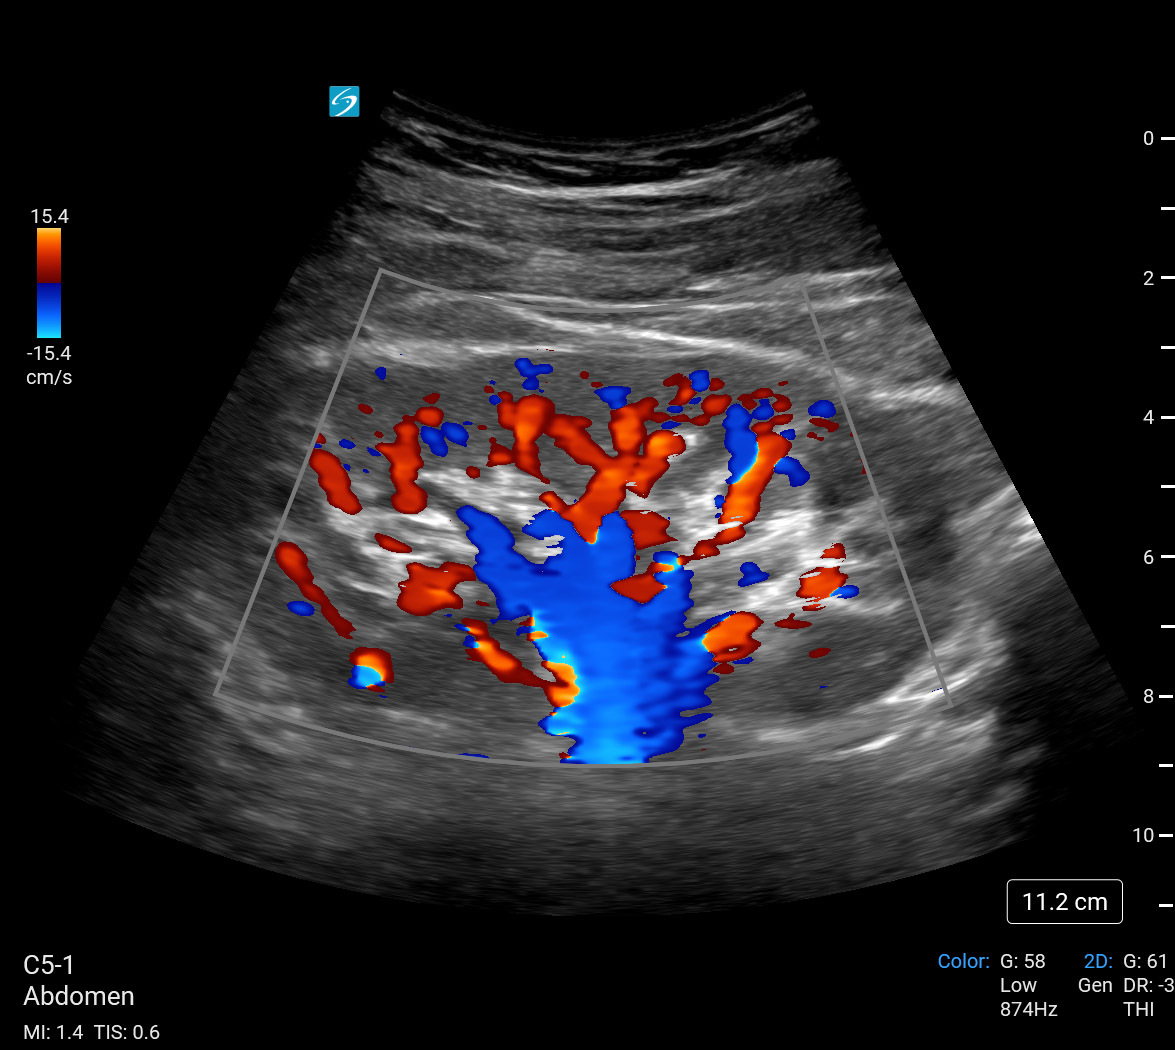

Imagen eFAST/RUSH de riñón derecho con Doppler de potencia en color

Flujo sanguíneo renal